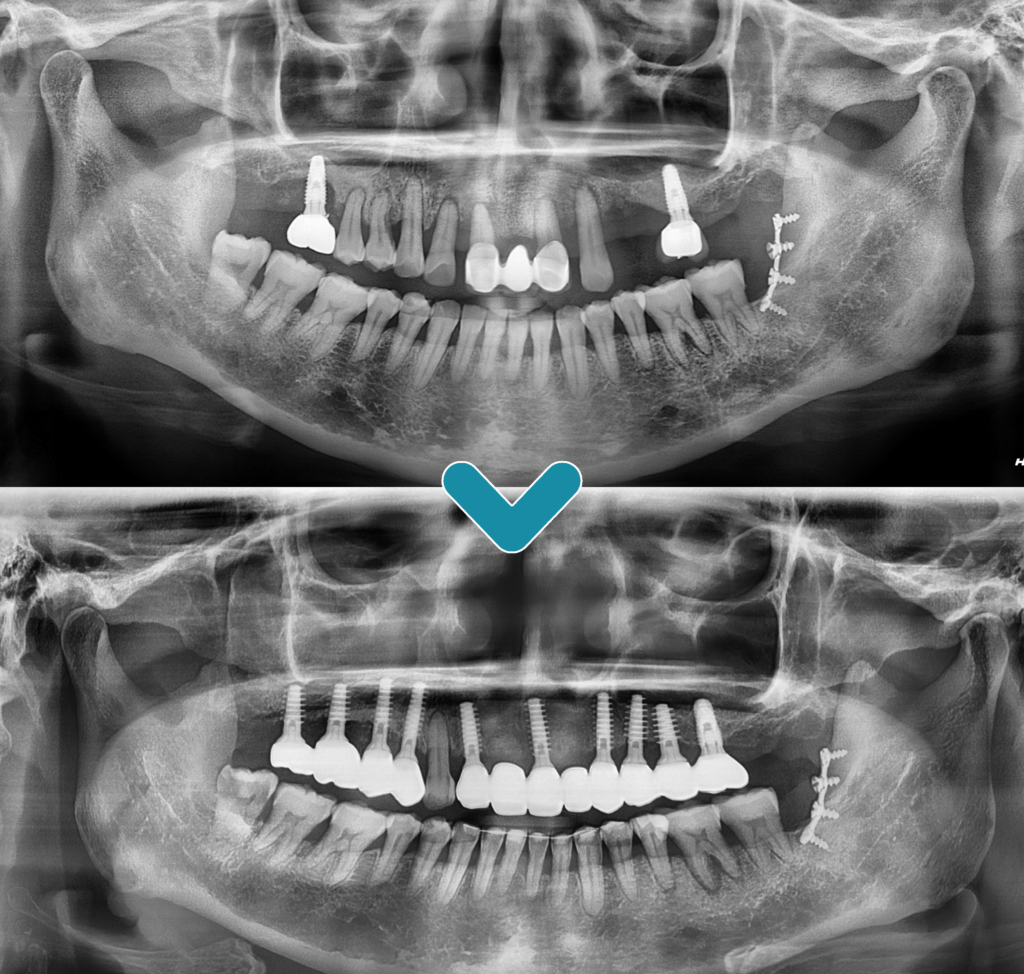

오늘은 예후가 좋지 않은

위쪽 자연치들을 발치한 후

전체 임플란트 식립을 진행하신

환.자분을 소개해 드리려고 합니다.

잇몸 절개 양을 줄인 최소침습 임플란트를

식립하여 마무리하였는데요.

이는 치조골 폭이 좁거나 상태가

좋지 않더라도 식립 가능하여

환.자의 치조골 크기와 형태에 맞는

임플란트 선택이 가능합니다.

더불어 골이식이나 골 형성 등의

부가적인 수술도 줄일 수 있고

일체.형의 바디로 감염이나 부러지는 등

위험성이 줄어들며 중간에 개입하는

지대주 없이 강한 보철 구조를 하고 있어

파절이나 나사가 풀리는 것과 같은

부작용이 발생할 우려가 적습니다.

또한 응력 분산이 뛰어나 내구성이 우수하며

미세 틈이 없어 음식물 끼임으로 인한 냄새,

염증 등이 감소하므로 건강한 잇몸 생성을

유지할 수 있습니다.